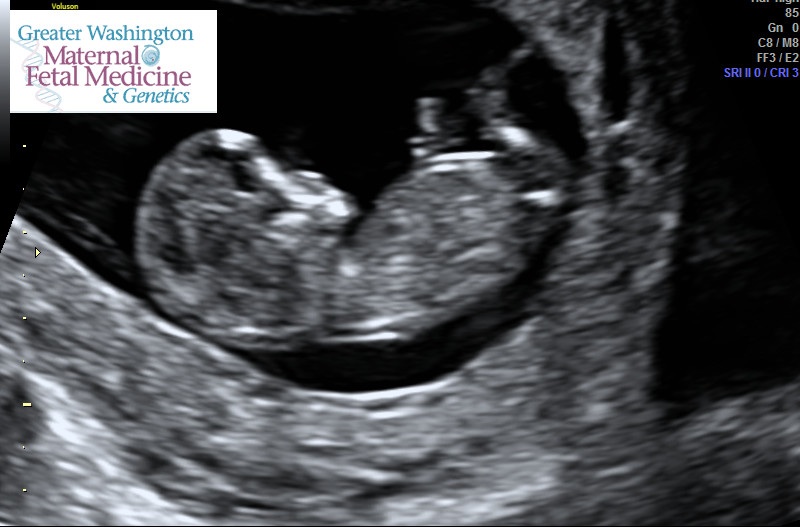

Does this count? Mommy's uterus and me! NTS normal... looks like Warner is going to have a brother! (of course to be confirmed at the AS but looked like an obvious wiener to me and to tech!)

Haha sorry I couldn't resist the classic crotch shot!